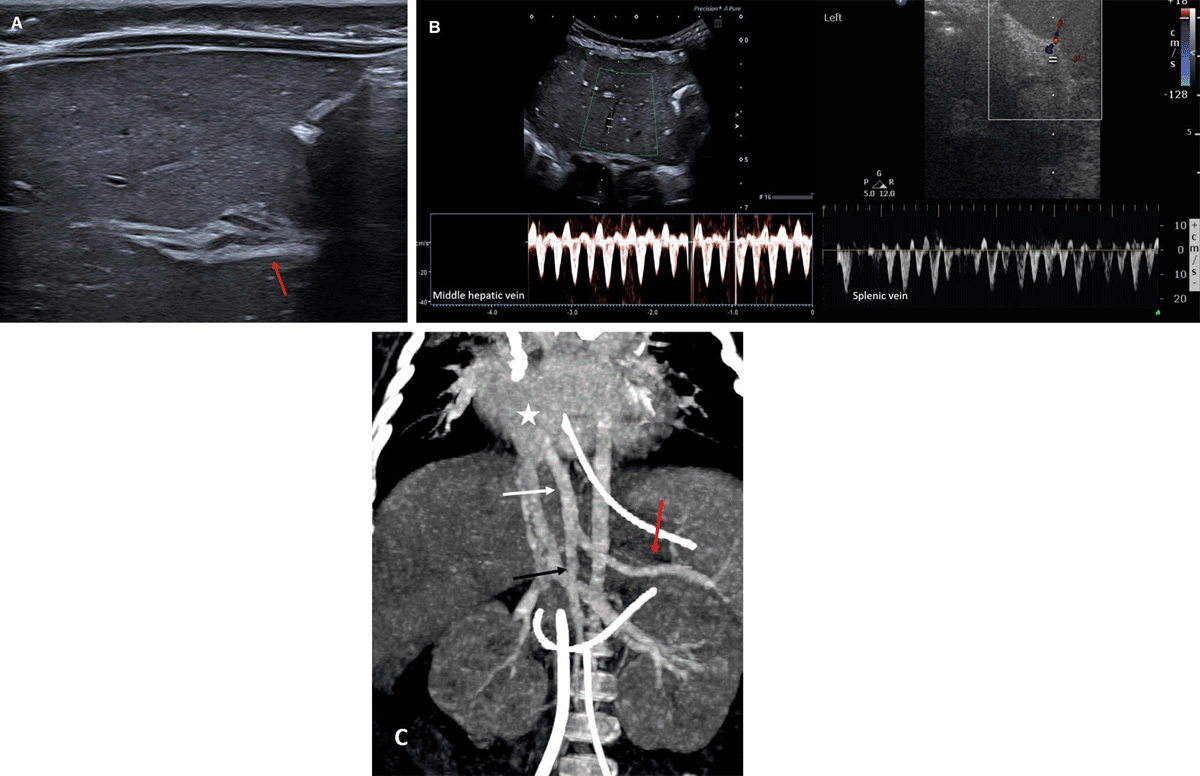

It revealed homogeneous liver parenchyma, normal gallbladder, and no dilatation of the biliary ducts. However, the portal vein could not be demonstrated. Where we would normally expect the intra-hepatic portal vein there was a hyperechoic smooth band of 3–4 mm (Figure A, arrow). No portal vein Doppler signal could be detected in the liver. Pulsed-wave Doppler in the hepatic and splenic veins showed the same flow pattern (Figure B), indicating a communication between the systemic and splanchnic veins. A contrast-enhanced computed tomography (CT) of the abdomen was performed to demonstrate properly the anatomy of the splanchnic veins. It confirmed a venous malformation, with confluence of the splenic and superior mesenteric vein into a common trunk that drained directly into the right atrium, also named “Abernethy malformation type 1b” (Figure C, coronal maximum intensity projection, red arrow: splenic vein, black arrow: superior mesenteric vein, white arrow: shunt, star: right atrium). The patient eventually died a month after surgery without being treated for the malformation.

Figure 1

A, B and C.